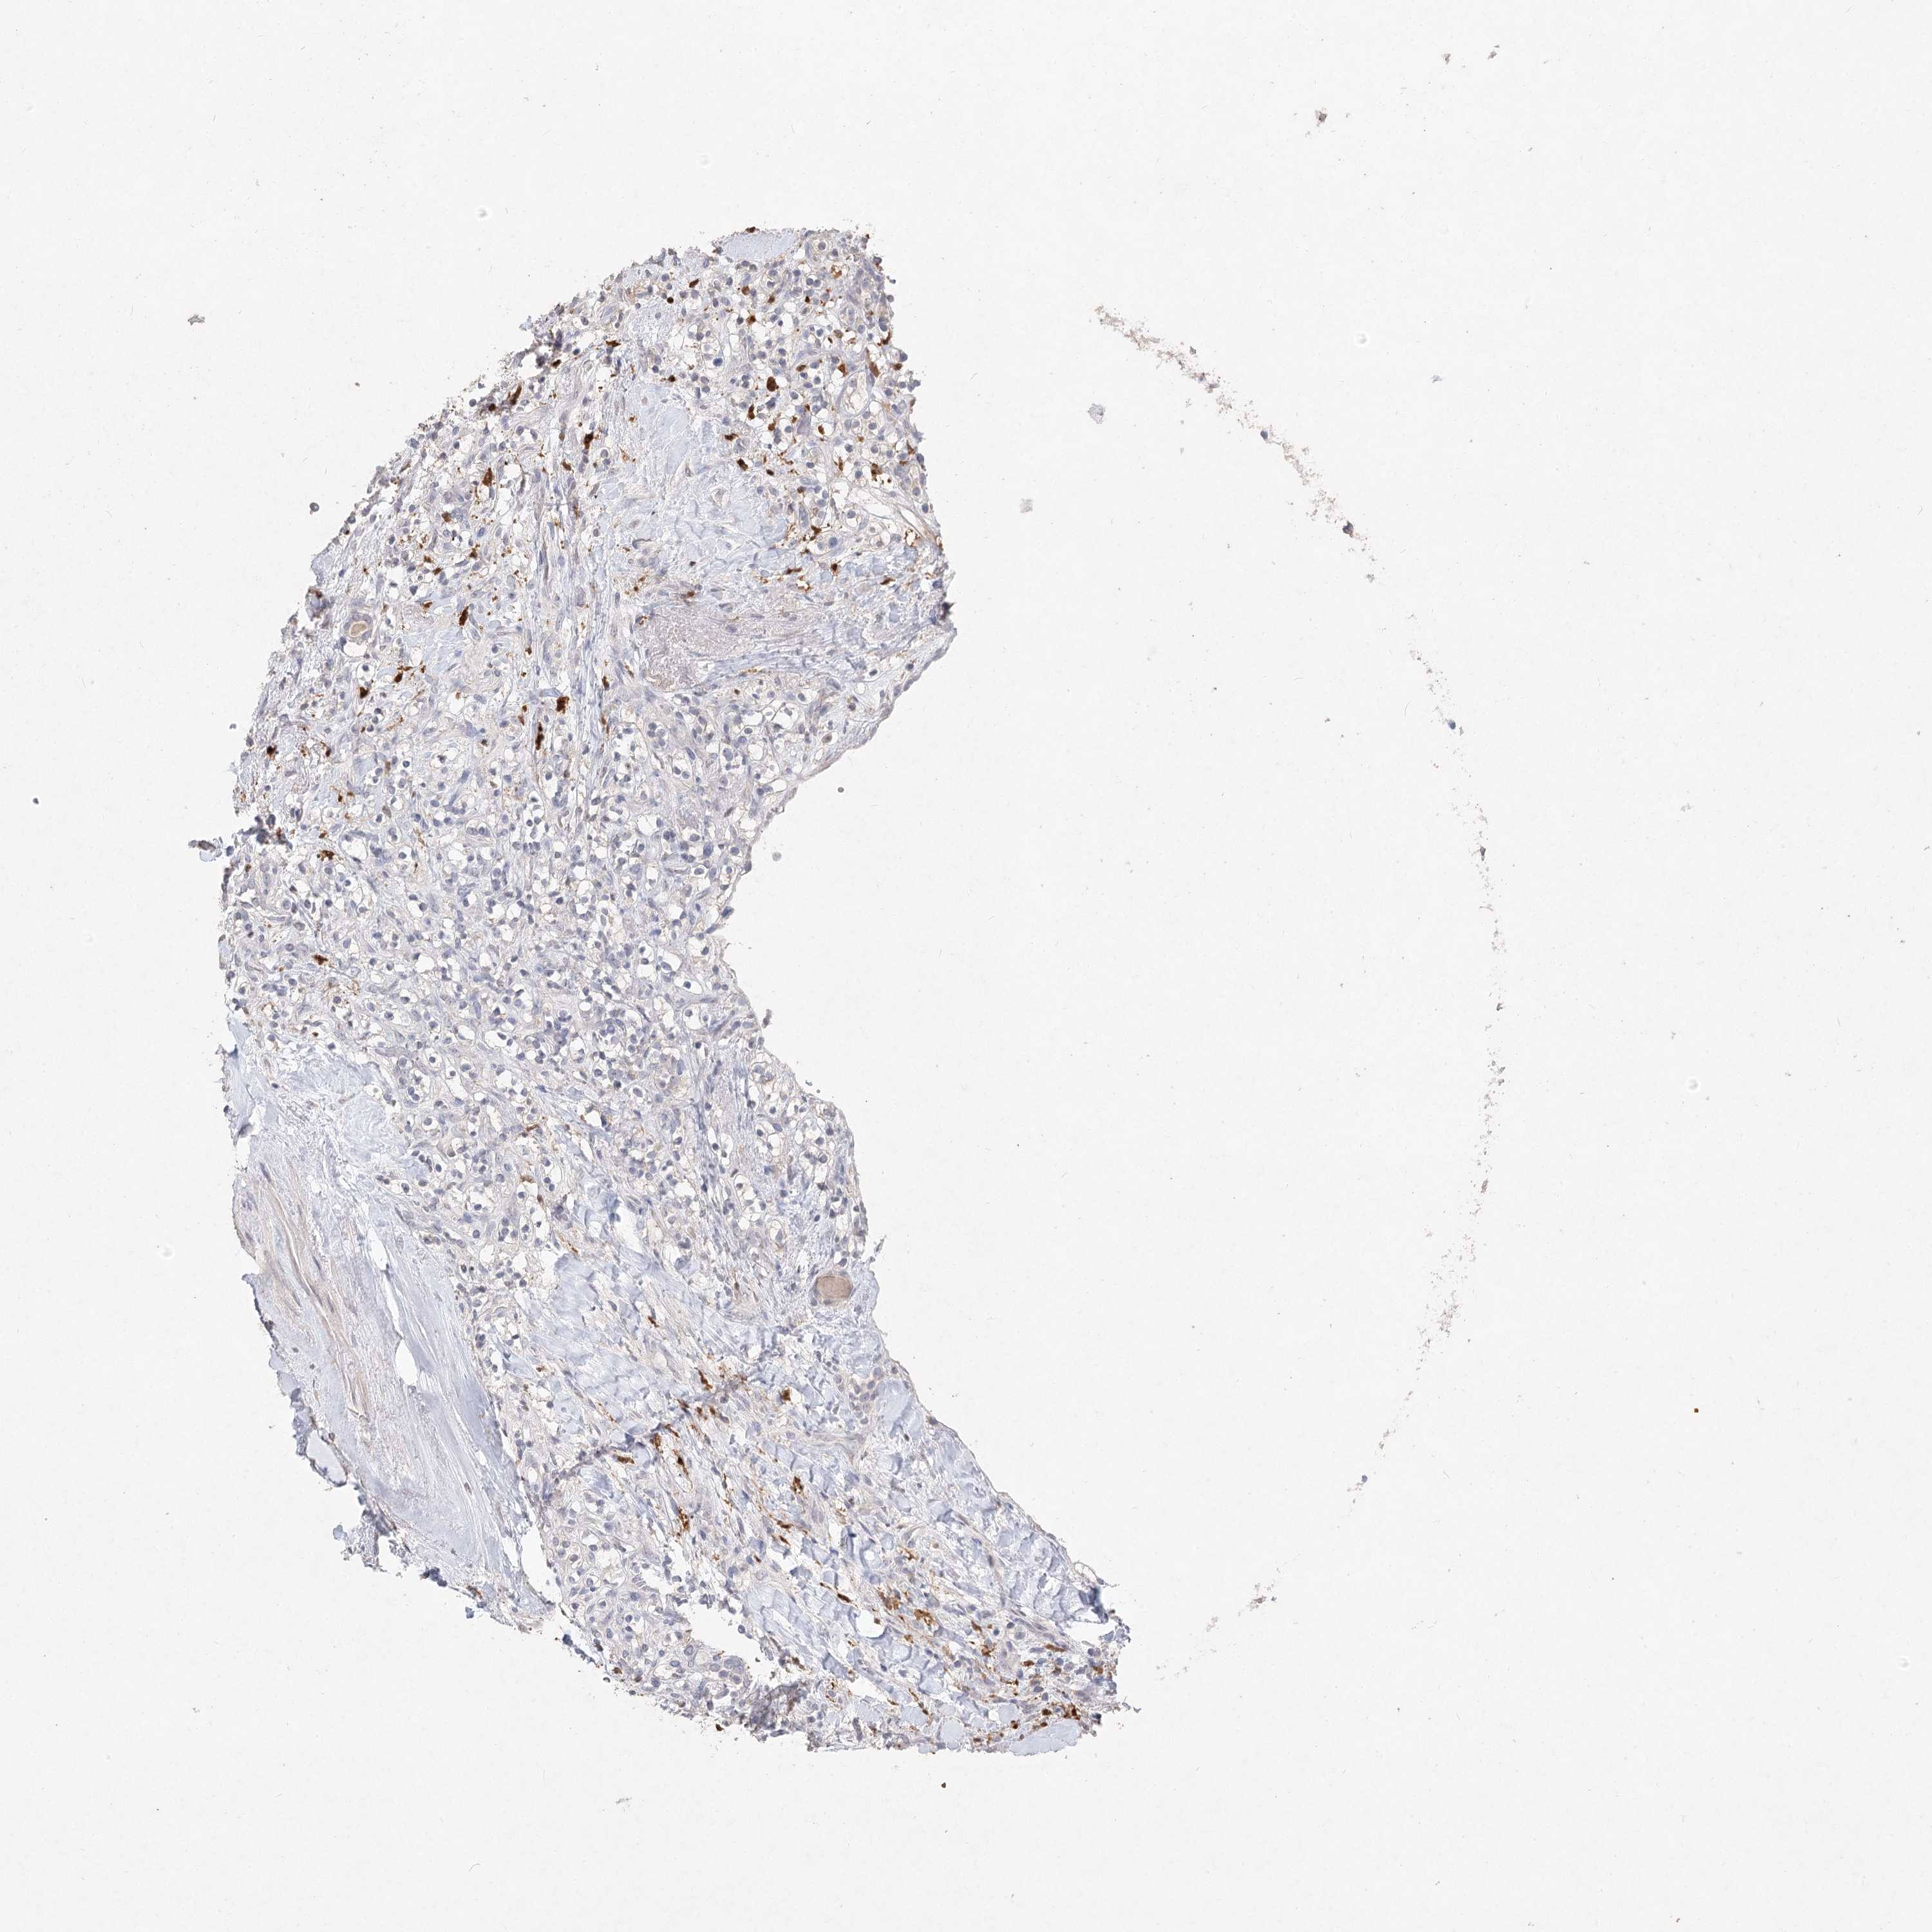

KIDNEY RENAL CLEAR CELL CARCINOMA (VALIDATION) - Interactive survival scatter ploti

The Survival Scatter plot shows the clinical status (i.e. dead or alive) for all individuals in the patient cohort, based on the same data that underlies the corresponding Kaplan-Meier plots. Patients that are alive at last time for follow-up are shown in blue and patients who have died during the study are shown in red.

The x-axis shows the expression levels (FPKM) of the investigated gene in the tumor tissue at the time of diagnosis. The y-axis shows the follow-up time after diagnosis (years). Both axes are complimented with kernel density curves demonstrating the data density over the axes. The top density plot shows the expression levels (FPKM) distribution among dead (red) and alive patients (blue). The right density plot shows the data density of the survived years of dead patients with high and low expression levels respectively, stratified using the cutoff indicated by the vertical dashed line through the Survival Scatter plot. This cutoff is automatically defined based on the FPKM cutoff that minimizes the p-score. The cutoff can be changed by dragging the vertical line or by entering a cutoff value in the square labeled "Current cut-off".

Under the Survival Scatter plot the p-score landscape (black curve; left axis) is shown together with dead median separation (red curve; right axis). Dead median separation is the difference in median mRNA expression between patients who have died with high and low expression, respectively. It is calculated as follows: median FPKM expression of dead patients with high expression - median FPKM expression of dead patients with low expression. This is intended to aid the user in visually exploring custom cutoffs and the associated p-scores and dead median separation.

Individual patient data is displayed and can be filtered by clicking on one or more of the category buttons on the top of the page. Categories describing expression level and patient information include: high, low, alive, dead, female, male and tumor stages. The scale of the x-axis can be toggled between linear and log-scale by clicking on the "x log" button. Mouse-over function shows TCGA ID, patient information and mRNA expression (FPKM) for each patient.

& Survival analysisi

Kaplan-Meier plots summarize results from analysis of correlation between mRNA expression level and patient survival. Patients were divided based on level of expression into one of the two groups "low" (under cut off) or "high" (over cut off). X-axis shows time for survival (years) and y-axis shows the probability of survival, where 1.0 corresponds to 100 percent.

ARSI is not prognostic in Kidney Renal Clear Cell Carcinoma (validation)

TCGA RNA samplesi

RNA-seq data is reported as average FPKM (number Fragments Per Kilobase of exon per Million reads), generated by the The Cancer Genome Atlas (TCGA) .

Normal distribution across the dataset is visualized with box plots, shown as median and 25th and 75th percentiles. Points are displayed as outliers if they are above or below 1.5 times the interquartile range. FPKM values of the individual samples are presented next to the box plot.

Average pTPM 0.8

Number of samples 100